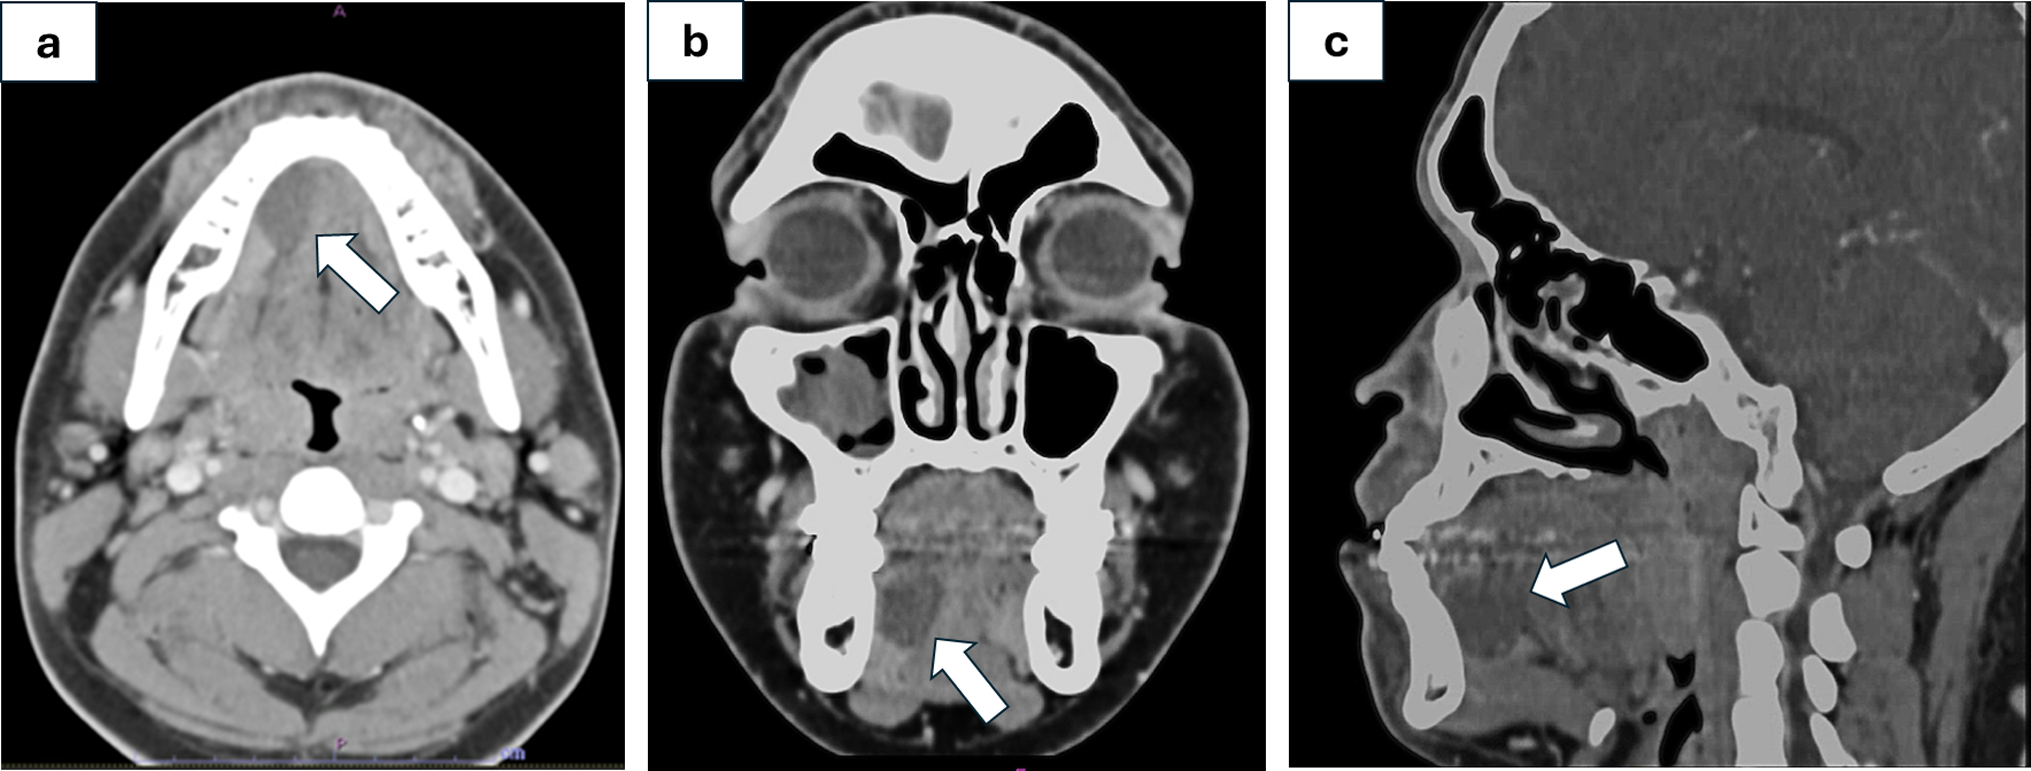

The extraoral examination was unremarkable. Intraoral examination revealed a 2 × 2 × 2 cm, raised, soft and mobile depressible swelling with normal color, of the right anterior floor of the mouth (Fig. 1). The clinical impression of the lesion was a ranula. Computed tomography (CT) examination demonstrated a 2.2 × 1.7 × 1.2 cm soft tissue density-based structure in the right anterior sublingual space (Fig. 2a–c). Preoperative laboratory studies were normal. Linear mucosal incision was made with a bovie electrocautery over the lesion. Blunt dissection was performed with Kelly forceps between mucosa, and the lesion was bluntly dissected to the level of the sublingual gland and completely excised (Fig. 3a, b).

Fig. 2

Computed tomography scan images show cystic mass appearing in the right anterior sublingual space (with arrow). a Coronal view. b Sagittal view. c Axial view